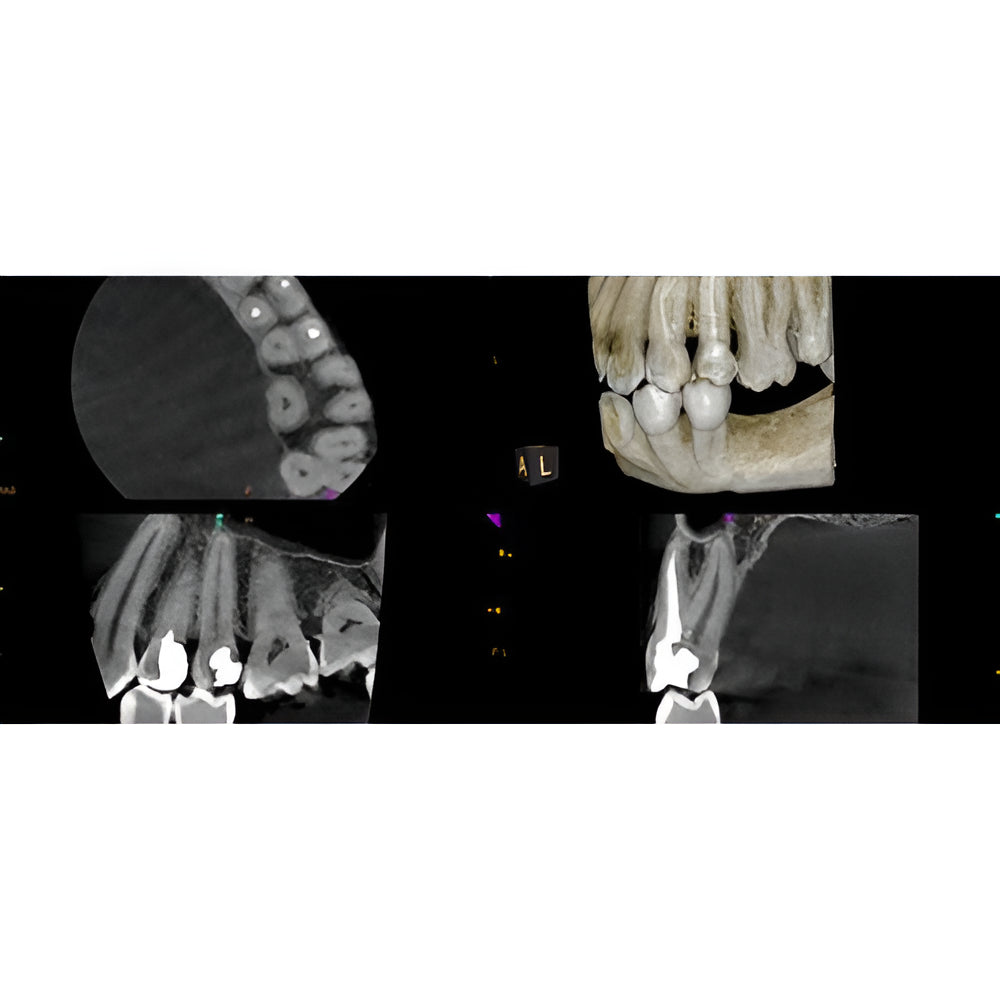

Enter a world of crystal-clear 3D images with the CS 8200 3D Access-a CBCT system that’s state-of-the-art, but intuitive and easy to use, taking your dental practice to the next level. Enjoy CBCT imaging that’s easier than you think and built on an open platform so that you can activate your future practice here and now.

- Versatile 4-in-1 solution ideal to expand treatment options

- Built on an open platform for a seamless workflow